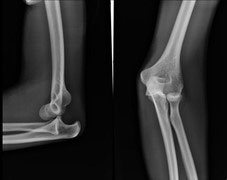

Imaging is an important part of the evaluation of elbow dislocations. X-rays are the first imaging ordered and an anteroposterior (AP) and lateral view should be obtained.

Posterior elbow dislocation lateral and AP view10

If there are no fractures on the X-ray, the elbow can be reduced immediately. If there are fractures, then the patient may require surgery and orthopedics should be consulted. Following reduction, the patient should have repeat X-rays to determine if the elbow was successfully reduced.